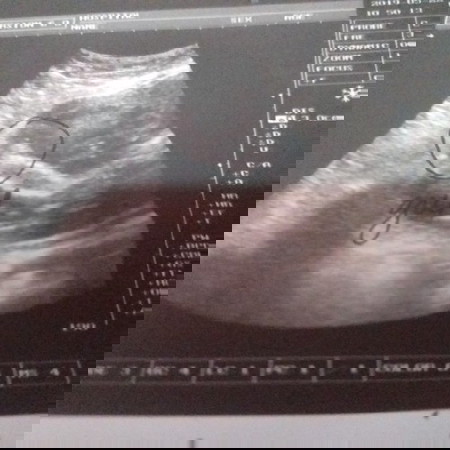

baby girl

Mga mommies pkitignan nga po kung baby girl po ang ganyan, sabi nung ng ultrasound baby girl po pag may guhit binilugan pa nga at isinulat yung girl..ganyan din po ba ang sa inyo?

Sa totoo lang hirap din ako umintindi ng ultrasound pic/video. Pero sa talas ng paningin ng mga sonologist, alam talaga nila kung girl o boy. Congrats pala at may baby girl ka na..